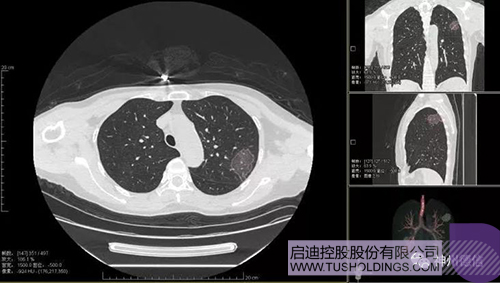

神州德信新冠肺炎检测及智能量化分析系统

九游·官方版在线入口战略投资企业神州德信作为国内领先的肺部影像人工智能企业,针对新型冠状病毒肺炎开发了智能检测及量化分析系统,并在陕西、重庆等地定点医院投入使用。该系统在疑似病例大规模快速筛查及精准诊断方面发挥了重要作用,特别是其具有的肺炎患者临床影像跟踪量化随访功能,为快速有效阻断疫情扩散提供了有力武器。